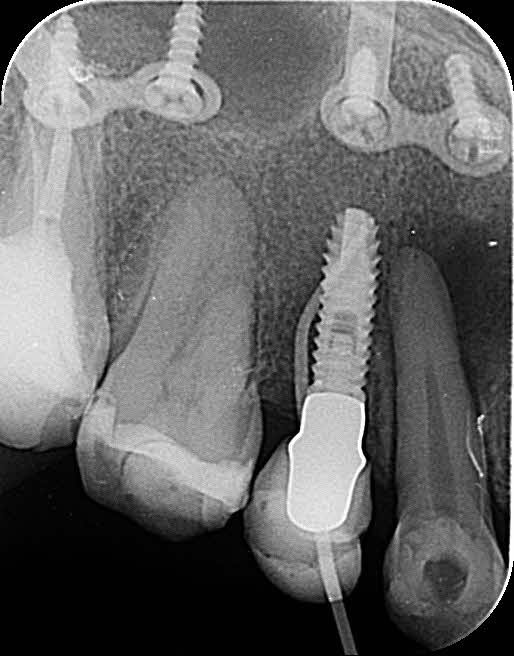

Hola chicos, podríais ayudarme a saber que marca es este implante, la paciente quiere cambiar la estetica de la protesis. se lo hicieron como en 2008, despues se hizo la [...]